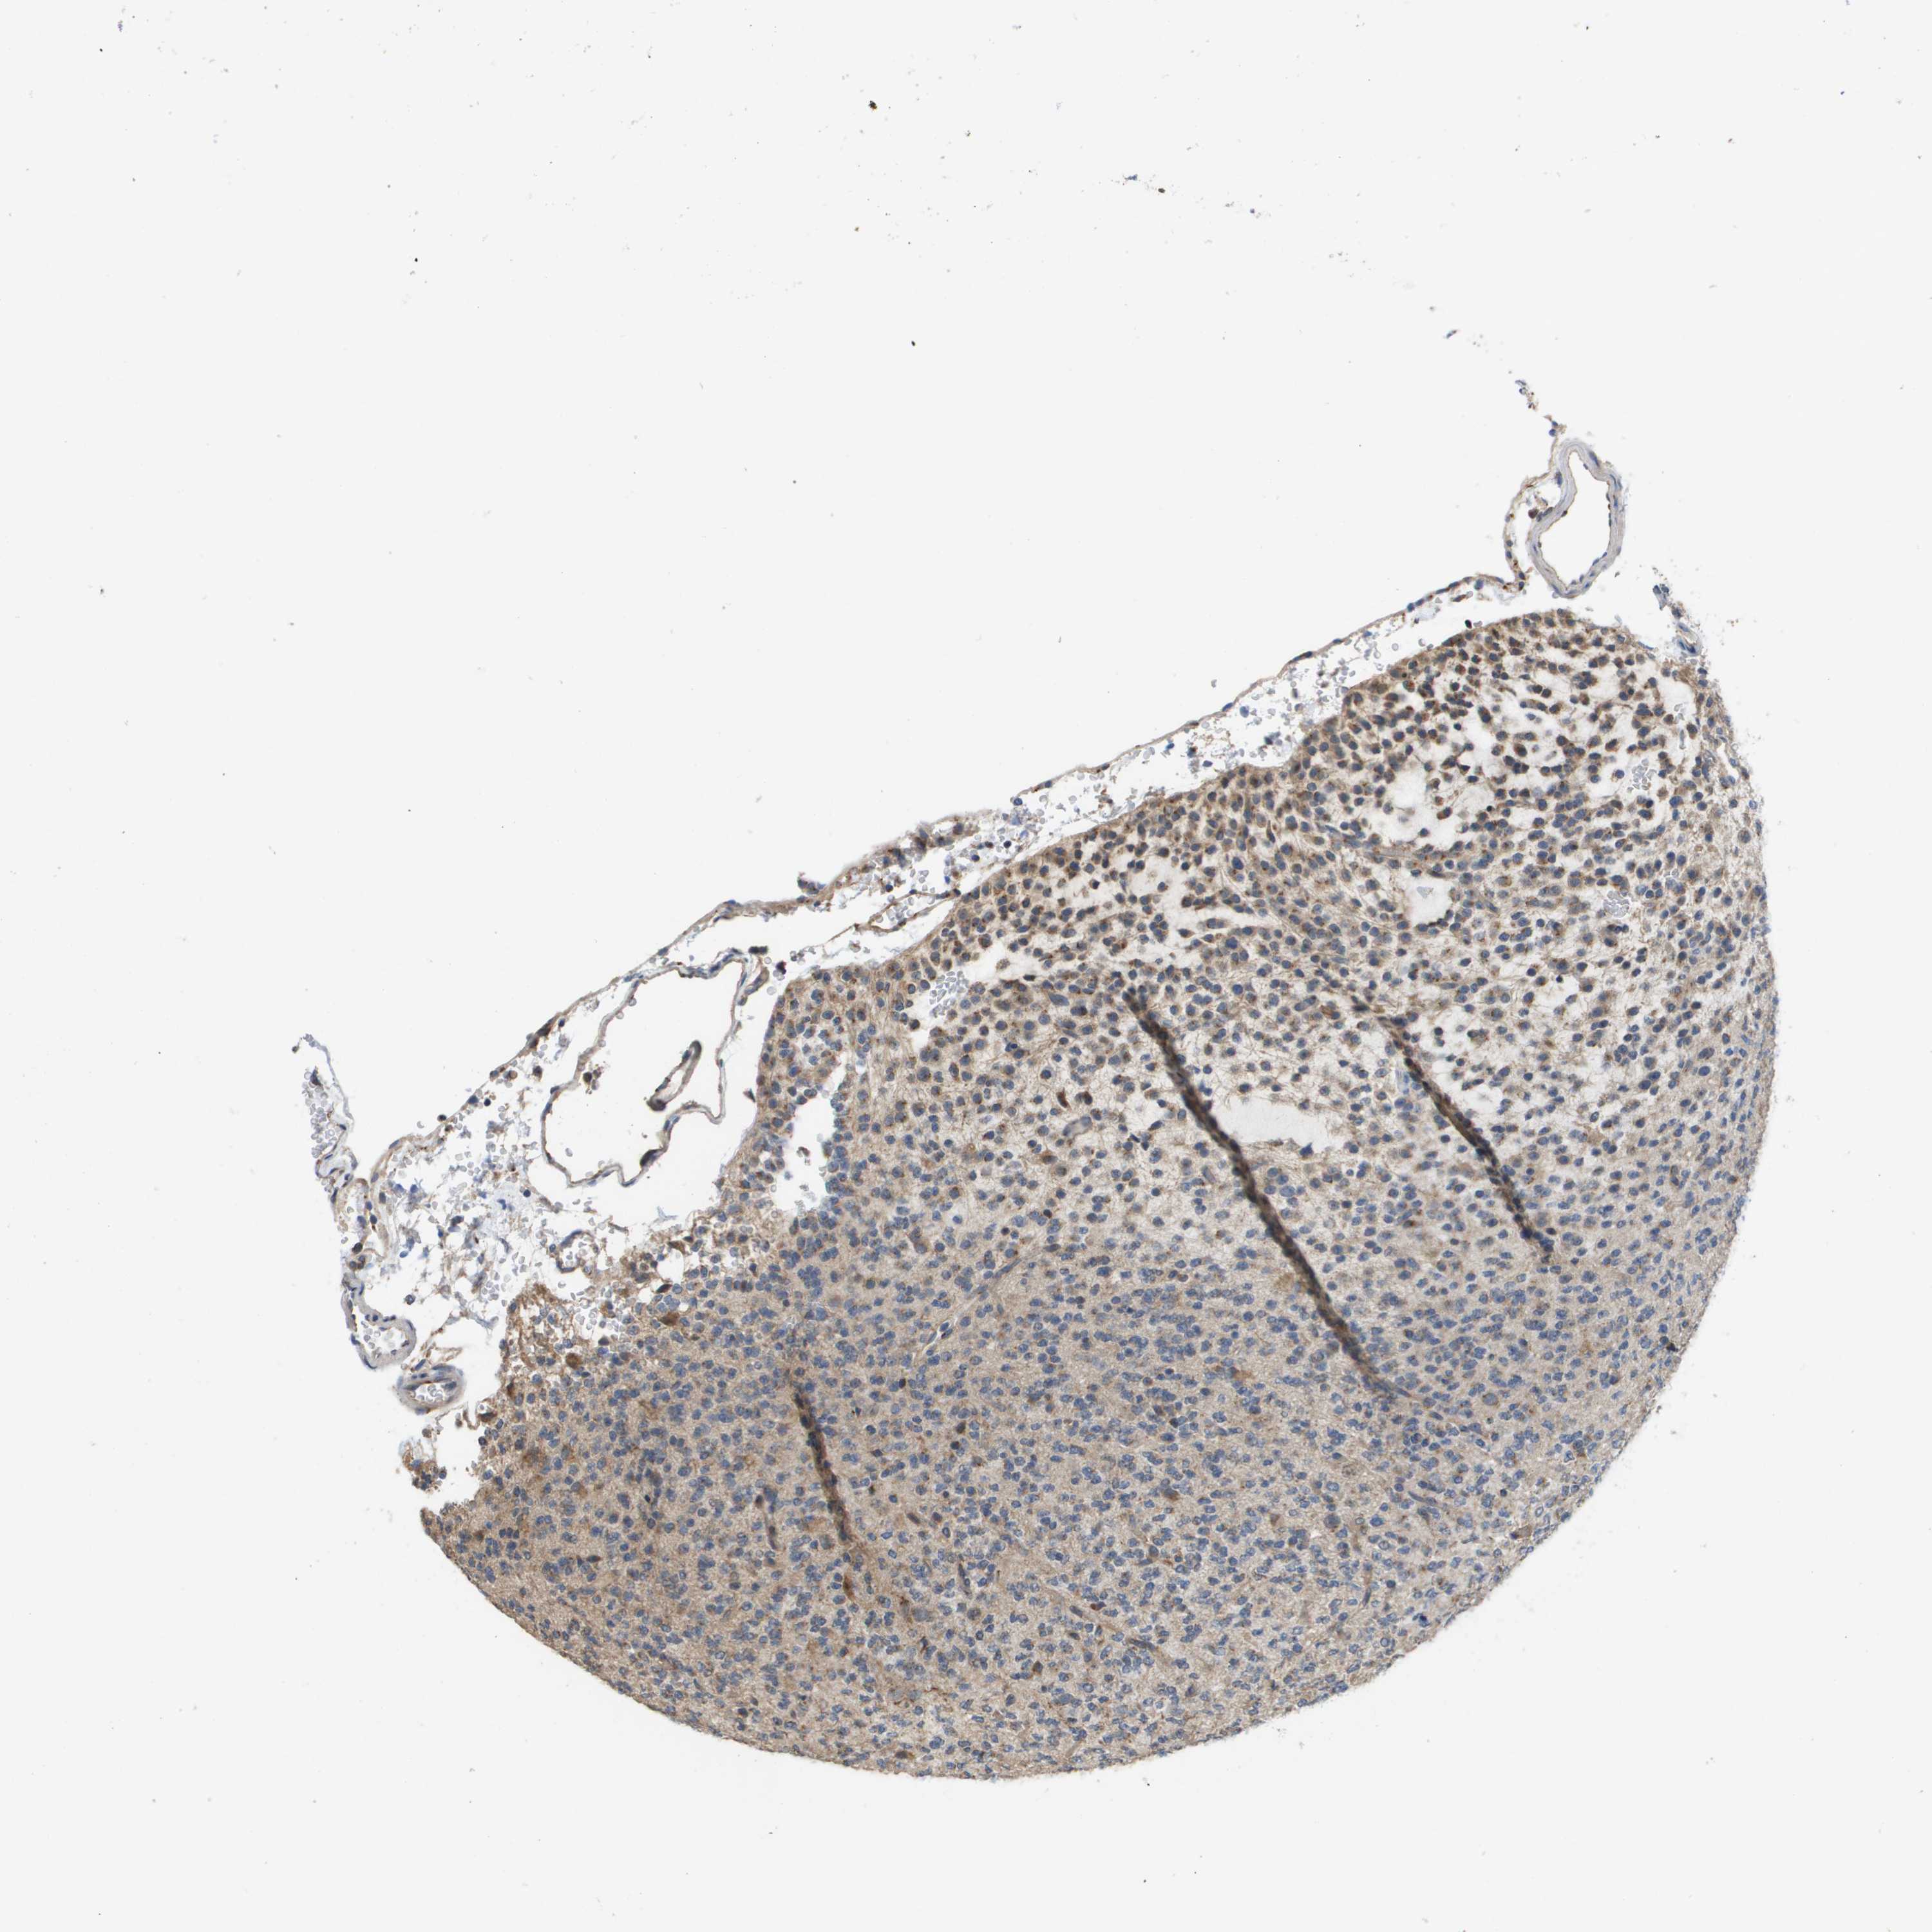

GLIOMA - Protein expressioni

A mouse-over function shows sample information and annotation data. Click on an image to view it in a full screen mode. Samples can be filtered based on level of antibody staining by selecting one or several of the following categories: high, medium, low and not detected. The assay and annotation is described here.

Note that samples used for immunohistochemistry by the Human Protein Atlas do not correspond to samples in the TCGA dataset.

Antibody stainingi

Antibody staining in the annotated cell types in the current human tissue is reported as not detected, low, medium, or high, based on conventional immunohistochemistry profiling in selected tissues. This score is based on the combination of the staining intensity and fraction of stained cells.

Each image is clickable and will lead to virtual microscopy that enables deeper exploration of all samples and also displays staining intensity scores, fraction scores and subcellular localization as well as patient and tissue information for each sample.

Antibody HPA006277

Antibody HPA006507

Antibody CAB017027

Staining

High

Medium

Low

Not detected

Intensity

Strong

Moderate

Weak

Negative

Quantity

>75%

75%-25%

<25%

None

Location

Nuclear

Cytoplasmic/membranous

Cytoplasmic/membranous,nuclear

Glioma, malignant, Low grade

Glioma, malignant, High grade